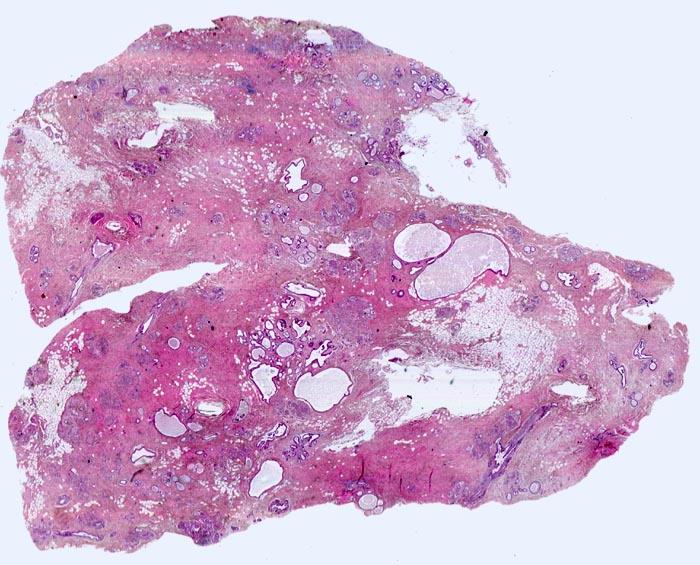

• Ausgeprägte Fibrose und zystisch erweiterte Gangstrukturen in organoider Anordnung.

• In der Mitte rechts einige Gänge mit gewöhnlicher intraduktaler Epithelhyperplasie ohne Atypie: Polymorphe, sich überlagernde spindelige Zellen. Fliessende Anordnung der Zellen. Schlitzförmige und irregulär geformte Lumina.

• Herdförmig apokrine Metaplasie des Drüsenepithels: hochprismatische Zellen mit sehr reichlichem feingranulärem eosinophilem Zytoplasma und runden Kernen.

• Rundlicher blauvioletter Mikrokalk in den Azini benigner Drüsenläppchen.

• Kolumnarzellveränderung: erweiterte Drüsen ausgekleidet von hochprismatischem Epithel mit apikalen Nasen (snouts) gefüllt mit Sekret und teilweise assoziiert mit Mikrokalk.

• Im Zentrum des Präparates stark erweiterte Gänge mit intraduktalen peripheren Papillomen.

• Alle Drüsen zeigen eine erhaltene äussere abgeflachte Myoepithelschicht mit hellem Zytoplasma.